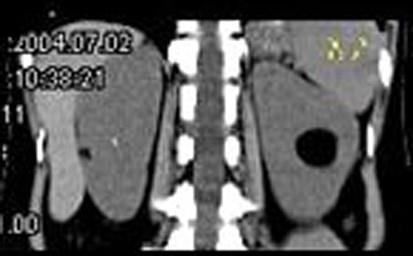

问题 女,38岁,体检时B超在左肾探及一中强回声光团,边界清,内部回声均匀,CT检查如图所示,下列说法正确的是 ( )

选项 A、考虑为左肾血管平滑肌脂肪瘤 B、考虑为左肾脂肪瘤 C、病灶与周围肾组织界限清楚 D、病灶密度为脂肪密度 E、左肾中部靠后方可见一类圆形低密度病灶

答案 BCDE